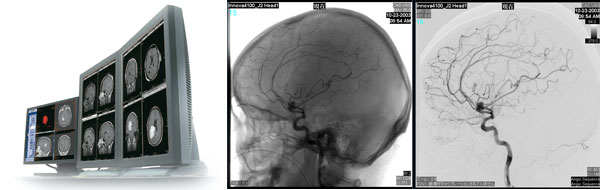

最左:Centricity PACS 3.2のワークステーション 右2枚:Centricity PACS3.2で再構成した頭部血管のDSA画像

さらに,医療施設内にある汎用端末への画像配信が可能なCentricity WebDX 2.0をオプション搭載することで,院内の様々な端末からもウェブ環境での画像参照が可能となるほか,画像参照時の使い勝手を向上する。またCentricity WebDX 2.0には,3D画像作成機能や,GEヘルスケア製PACSで初めて,高精細な血管像の描出を実現するデジタルサブトラクション(DSA)機能を搭載,特に脳神経外科領域の診断支援に貢献する。

具体的には,CTやMRIの撮影画像を同一患者の過去の画像と比較する際に表示サイズを自動調節するサイズシンク(FOV同期),使用頻度の高い機能に対するショートカットキー,医療カンファレンス(症例検討会)などに役立つユーザーごとのブックマーク機能など,国内の顧客ニーズの高かった機能を搭載している。また,2,000枚を超える最新CTの断層像を3秒以内に表示可能な,業界でも高い水準を誇る画像圧縮・高速転送技術を搭載するなど,装置のデジタル化とフィルムレス運用の進展に伴って画像データ量が急増する環境においても,高い利便性や迅速な画像表示を実現し,読影医の診断効率を向上させる。